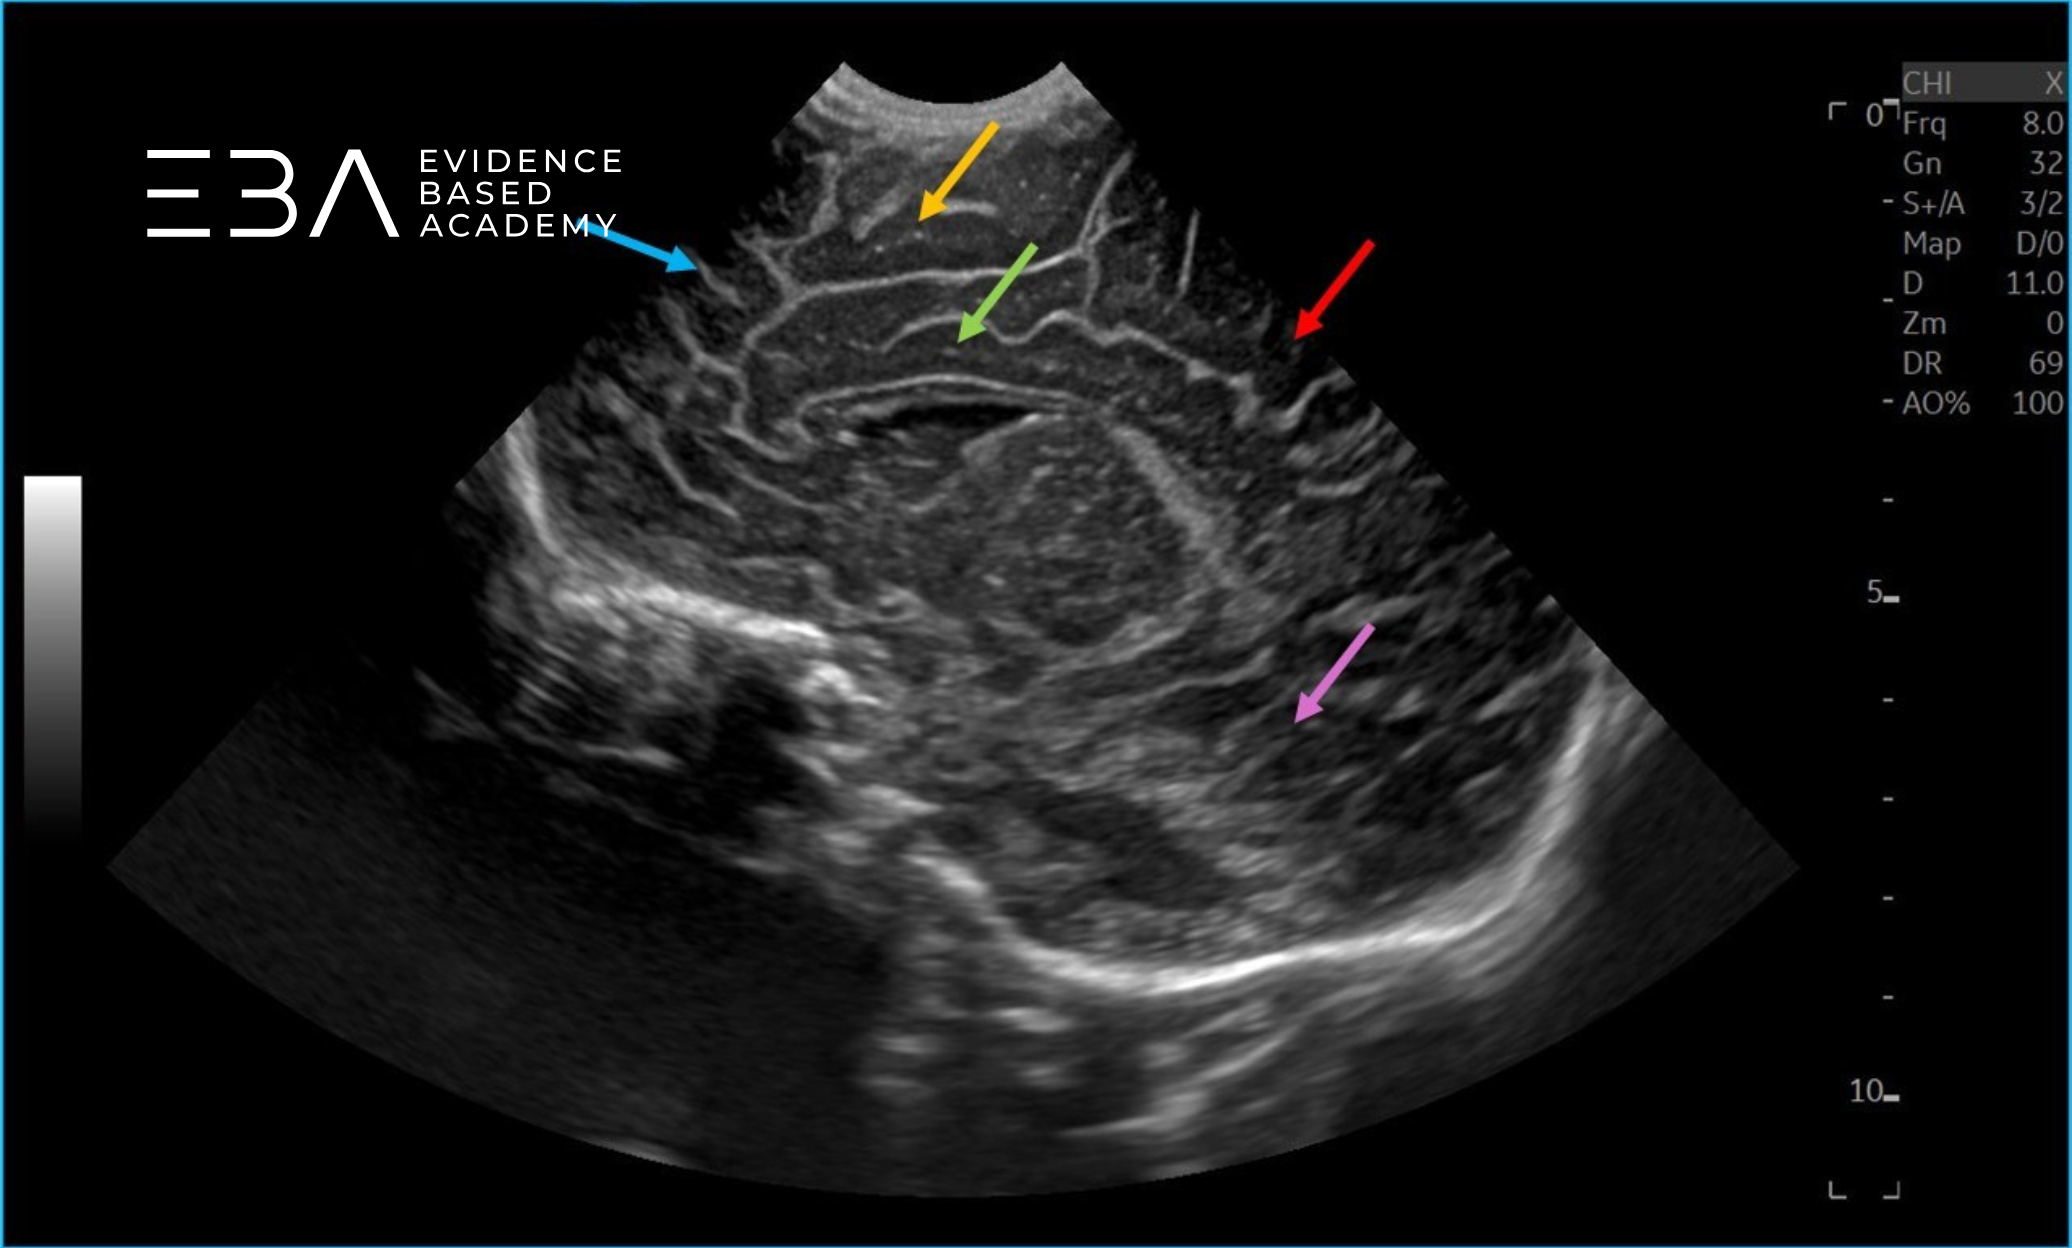

zdj. 5a

Głowica liniowa – badanie przez łuskę kości skroniowej. Konary mózgu (żółte strzałki), wodociąg mózgu (czerwona strzałka).